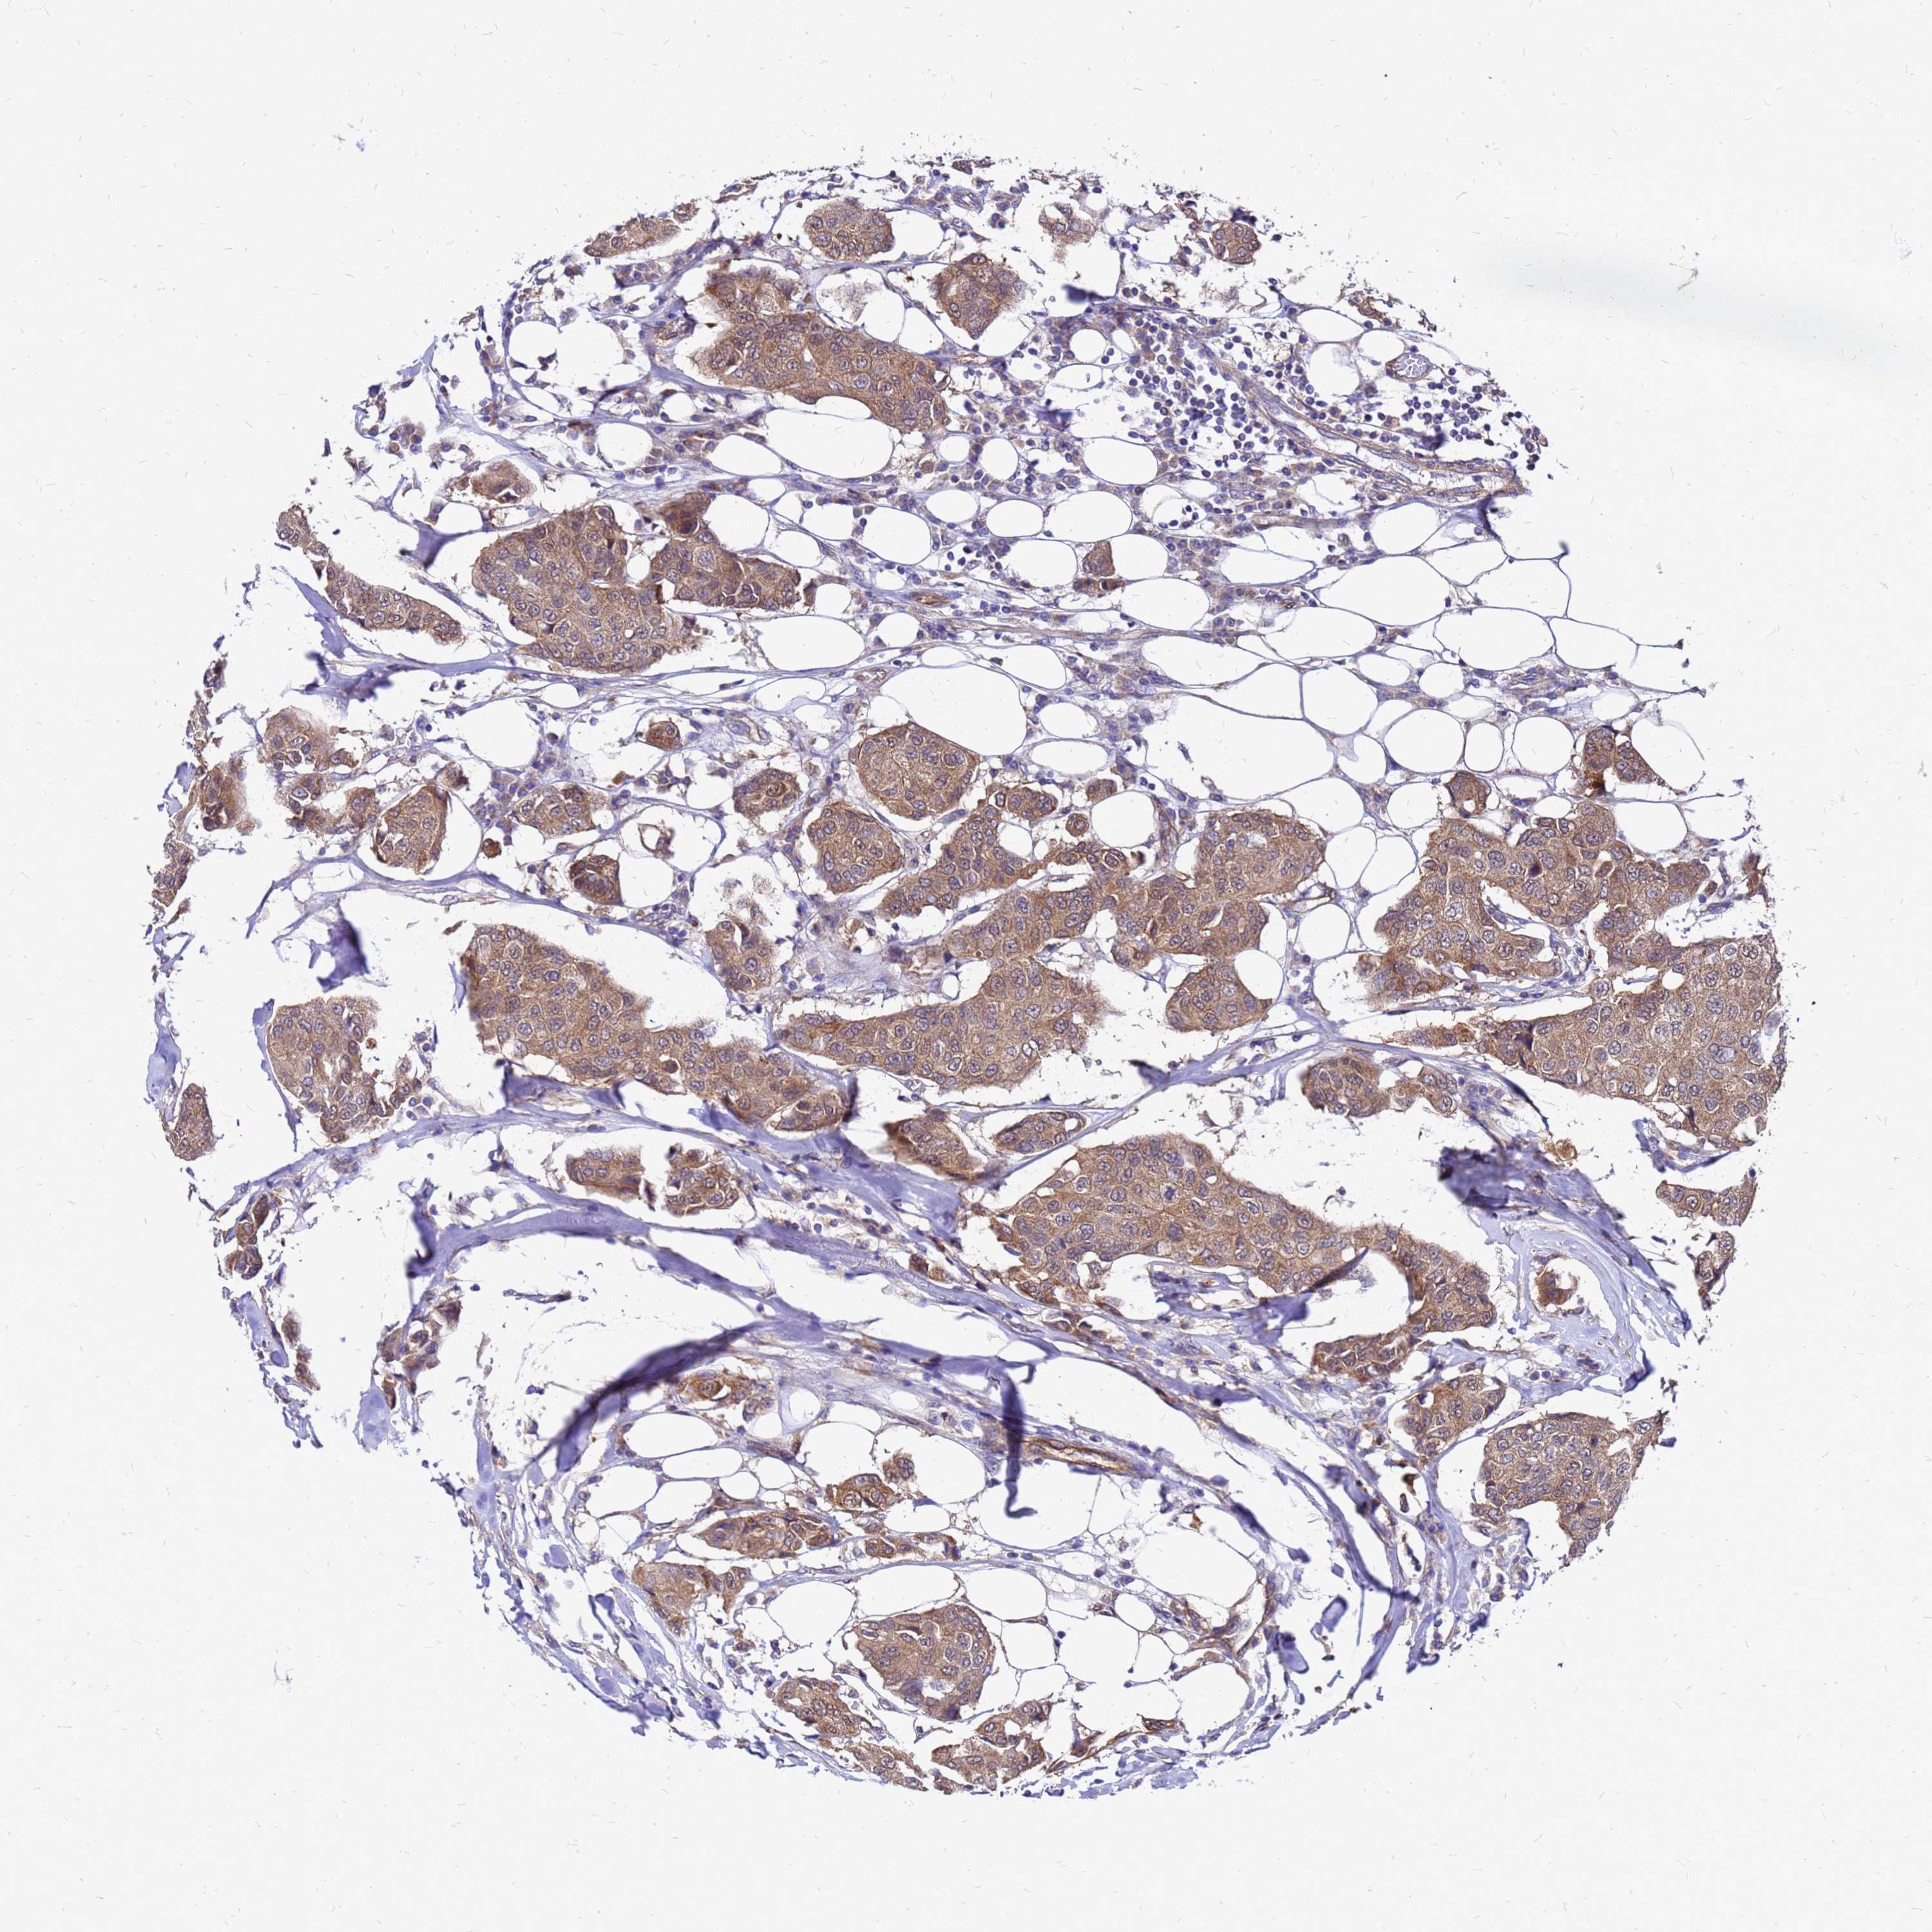

CANCER BREAST CANCER Show tissue menu

BRCA TCGA BRCA VALIDATION PROTEIN EXPRESSION